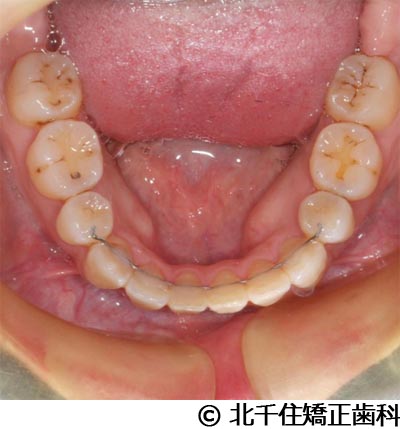

【症例4】下顎前突

- 治療前

- 治療後

- 治療名

- 下顎前突

- 費用

- 1,226,000円(税込)

- 期間

- 2年10ヵ月

- 治療回数

- 32回

- 通院頻度

- 1ヵ月ごと

- 年齢・性別

- 28歳5ヵ月・女性(初診時)

治療内容

-

患者様の症状

主訴:デコボコ、笑顔のとき歯がきれいに見えるようにしたい

治療方法

骨格性の下顎前突および開咬、上顎第二小臼歯と下顎第一小臼歯4本抜歯してワイヤー矯正(セラミックブラケット)。

治療結果

骨格性下顎前突および開咬に対し、抜歯を併用した矯正治療により歯列および咬合関係の調整を行った症例である。治療後は保定装置を使用し、歯列および咬合の安定維持を目的として定期的な経過観察を行っている。

※治療結果は個人差があります。

治療を行う上での注意点(リスク・副作用)

歯磨き不良に伴うカリエスや歯周病、歯根吸収など。